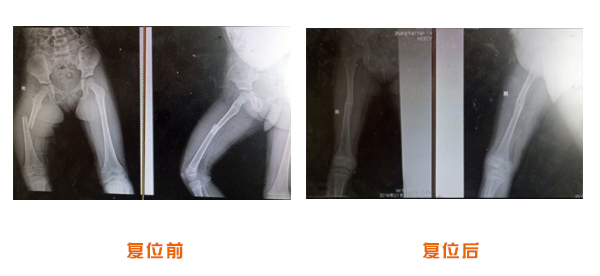

復(fù)位前后對(duì)比